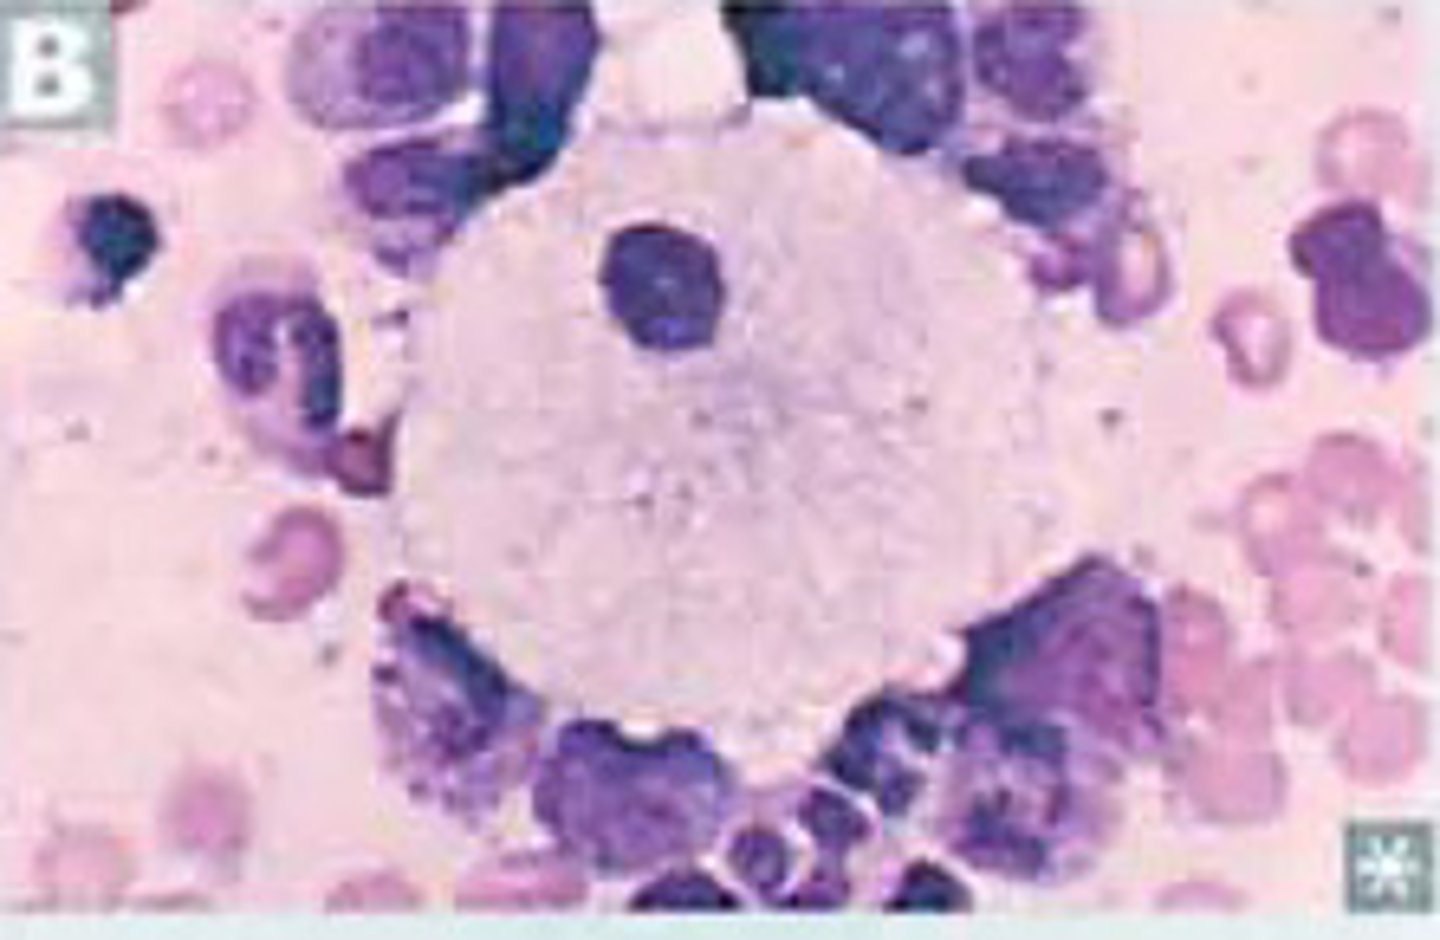

Hepatosplenomgaly, pancytopenia, osteoporosis, aseptic necrosis of femur, bone crises in child

Gaucher disease macrophage (glucocerebrosidase deficiency)

#1 lysosomal storage disease

Build up of glucocerbroside

"Crinkled tissue paper cells"